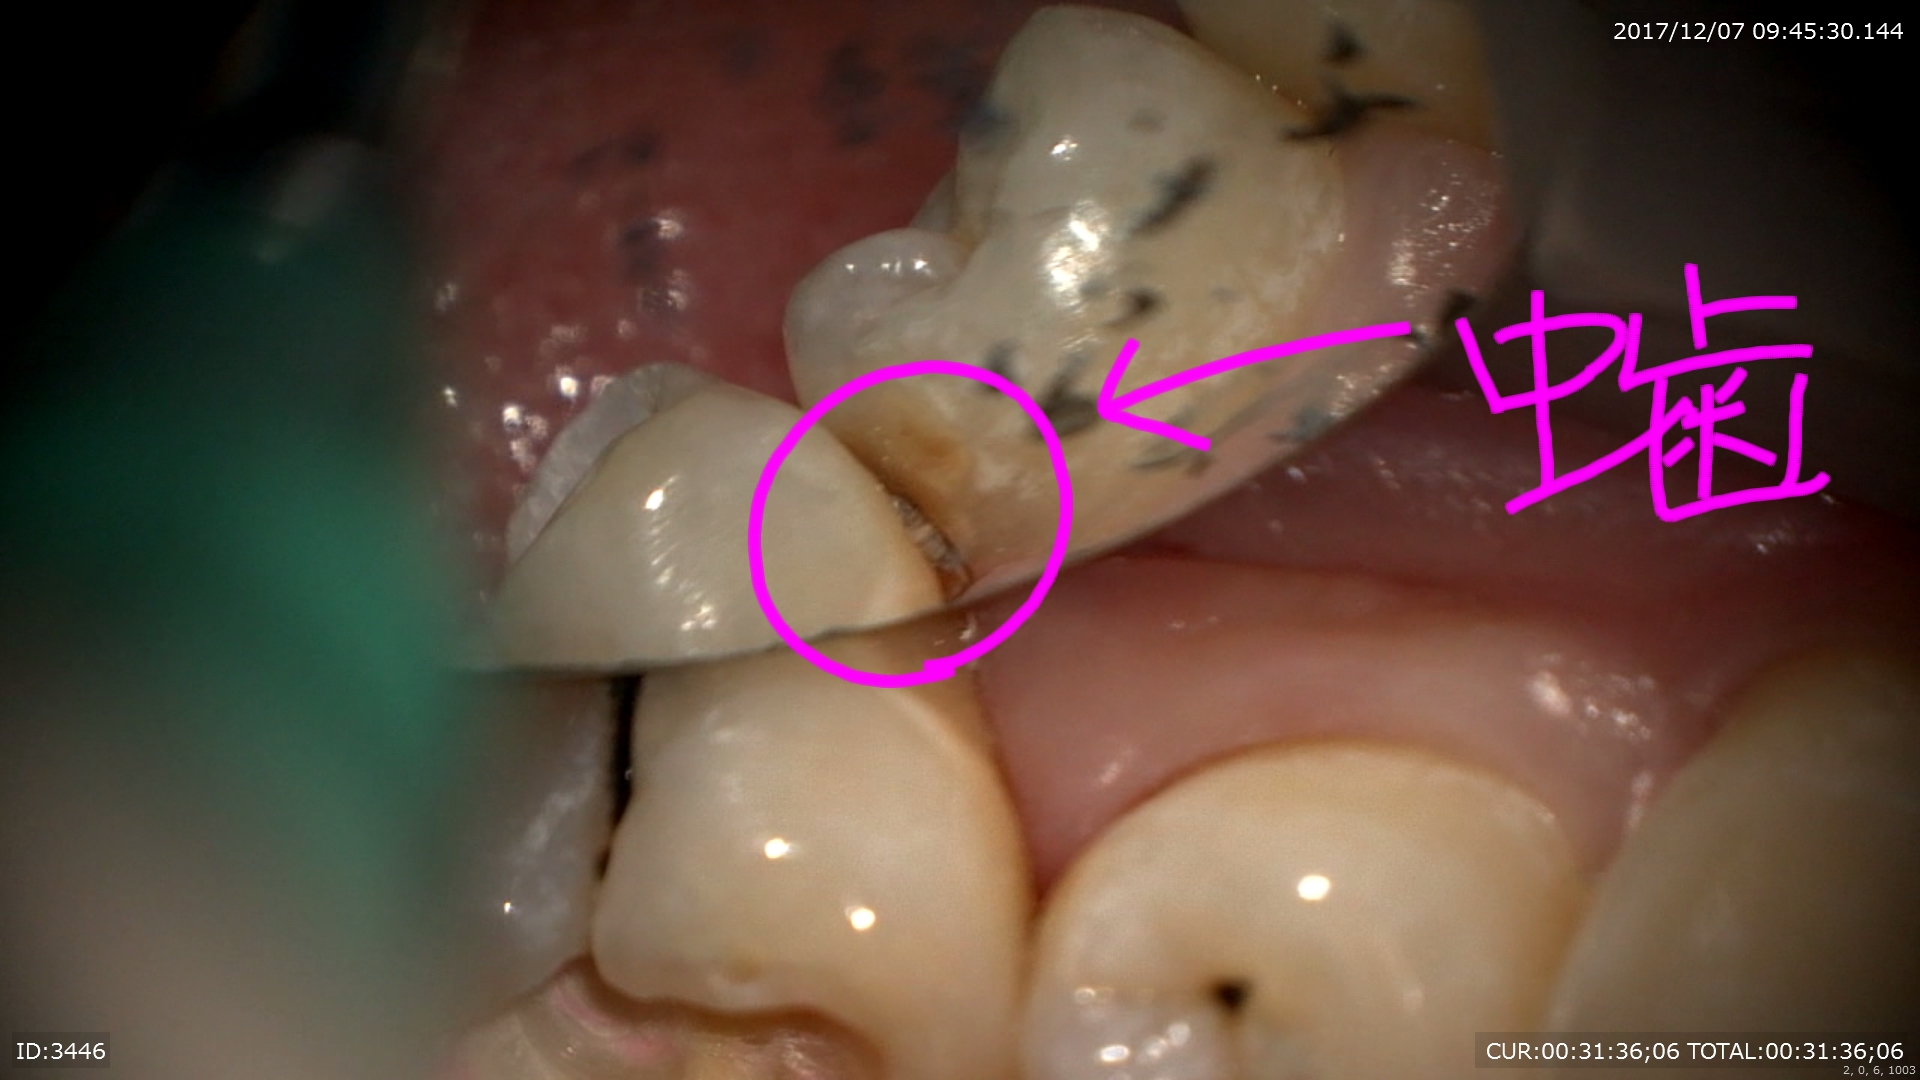

怖いのはここから。この虫歯を追従すると

ザクザク深いところまで。神経に近い。

隣の歯まで転移しています。

ほら隣の歯も。マイクロスコープですからここまで見えます。